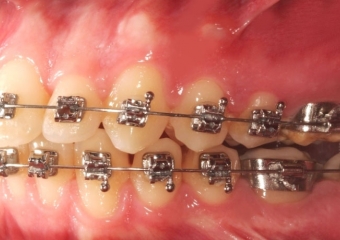

Mordida inicial - Clínica Cliniface

Mordida inicial

Mordida após cirurgia realizada em 2015 - Clínica Cliniface

Mordida após cirurgia realizada em 2015

Mordida após cirurgia (Controle de 1 anos e 5 meses) - Clínica Cliniface

Mordida após cirurgia (Controle de 1 anos e 5 meses)